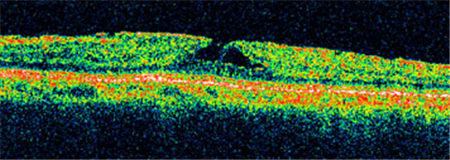

Ⅰ期黃斑裂孔通常無(wú)需手術(shù),若裂孔惡化至Ⅱ-Ⅳ期就需要考慮進(jìn)行手術(shù)治療。上海眼科醫(yī)院排名通過(guò)學(xué)相干斷層掃描來(lái)診斷黃斑裂孔,可清楚照出玻璃體及視網(wǎng)膜的情況,了解患者黃斑裂孔的大小、位置等。